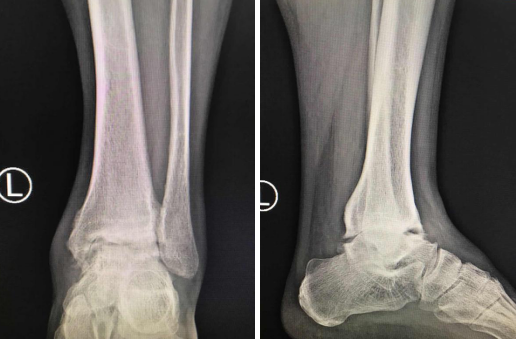

术前X片——终末期踝关节炎表现

周一正好是足踝科大科主任、副院长石荣剑主任医师坐诊,石院长听了病情,给王师傅做了检查,发现其踝关节已经严重破坏,且疼痛严重,已发展为左踝终末期踝关节炎,考虑进行微创关节镜下踝关节融合手术。